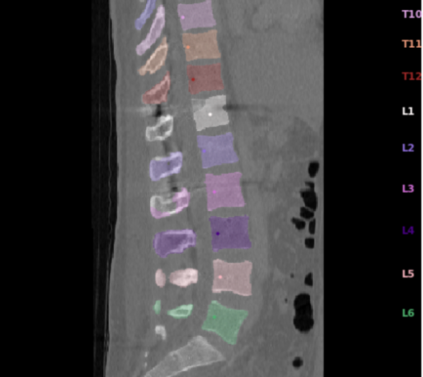

Vertebrae localization, segmentation and identification in CT images is key to numerous clinical applications. While deep learning strategies have brought to this field significant improvements over recent years, transitional and pathological vertebrae are still plaguing most existing approaches as a consequence of their poor representation in training datasets. Alternatively, proposed non-learning based methods take benefit of prior knowledge to handle such particular cases. In this work we propose to combine both strategies. To this purpose we introduce an iterative cycle in which individual vertebrae are recursively localized, segmented and identified using deep-networks, while anatomic consistency is enforced using statistical priors. In this strategy, the transitional vertebrae identification is handled by encoding their configurations in a graphical model that aggregates local deep-network predictions into an anatomically consistent final result. Our approach achieves state-of-the-art results on the VerSe20 challenge benchmark, and outperforms all methods on transitional vertebrae as well as the generalization to the VerSe19 challenge benchmark. Furthermore, our method can detect and report inconsistent spine regions that do not satisfy the anatomic consistency priors. Our code and model are openly available for research purposes.